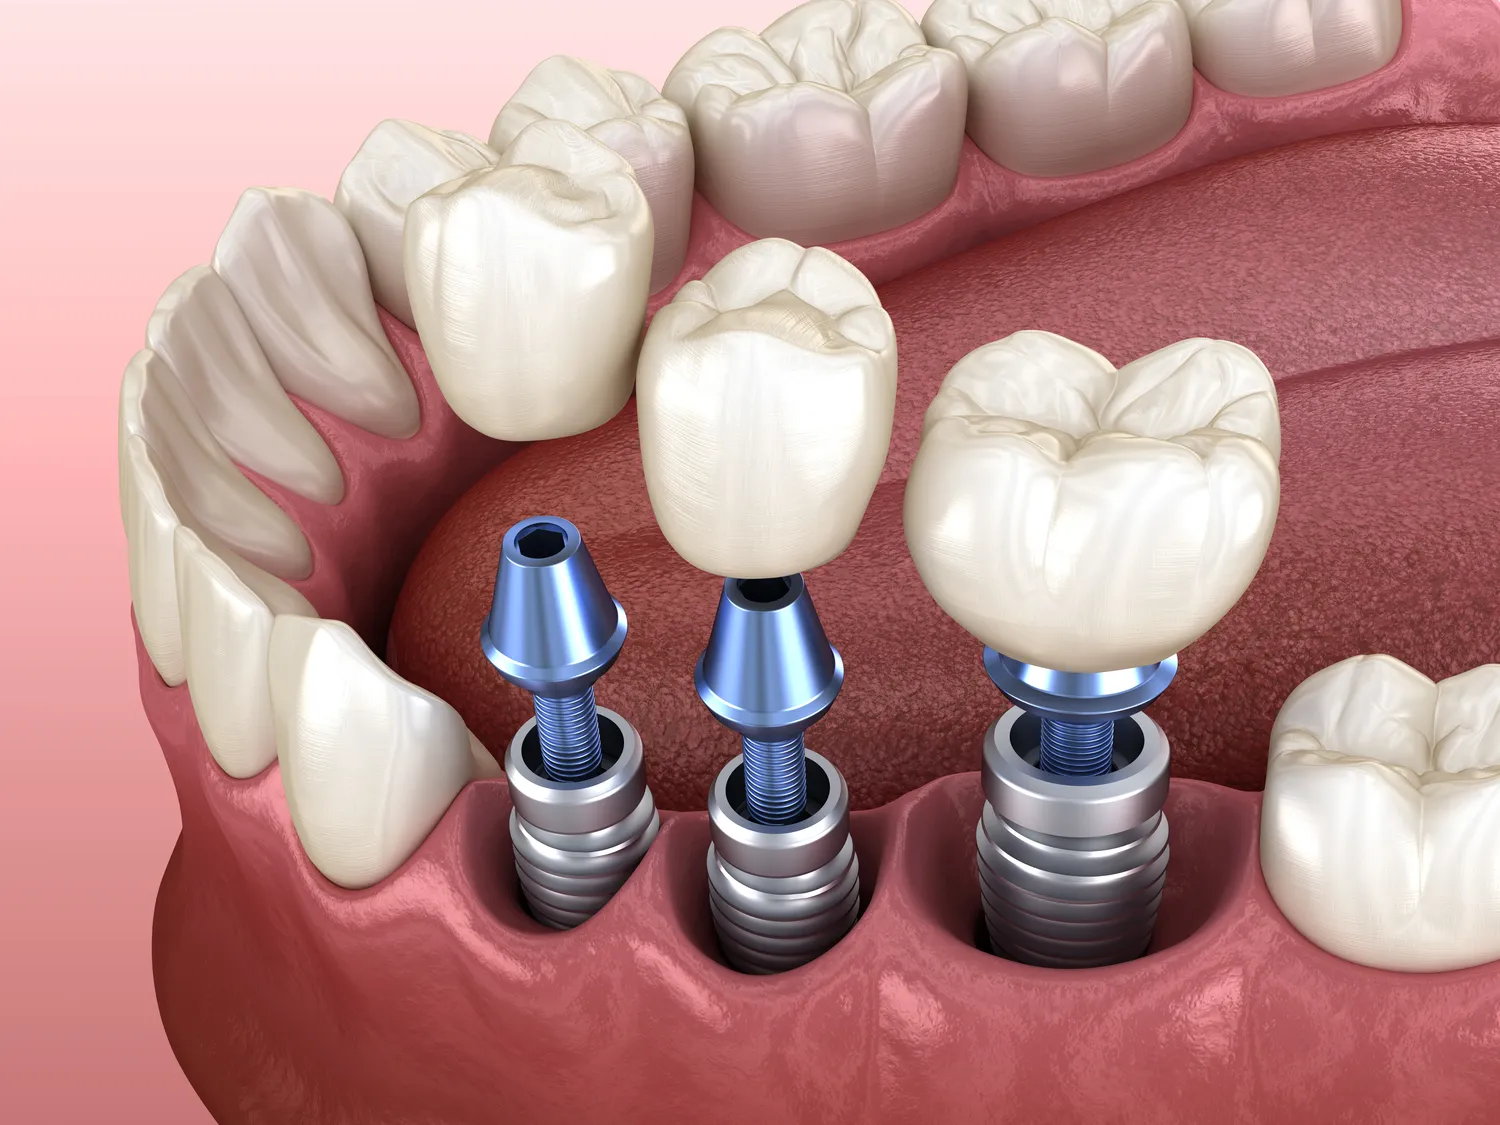

Wstawianie implantów zębowych to proces, który składa się z kilku kluczowych etapów, mających na celu zapewnienie trwałego i estetycznego efektu. Pierwszym krokiem jest dokładna diagnostyka, która obejmuje zdjęcia rentgenowskie oraz badania kliniczne. Lekarz stomatolog ocenia stan kości, aby ustalić, czy pacjent jest odpowiednim kandydatem do zabiegu. Następnie, po zakwalifikowaniu pacjenta, przeprowadza się zabieg chirurgiczny polegający na umieszczeniu implantu w kości szczęki lub żuchwy. Implant jest wykonany z biokompatybilnych materiałów, co pozwala na integrację z tkankami kostnymi. Po umieszczeniu implantu następuje okres gojenia, który może trwać od kilku tygodni do kilku miesięcy. W tym czasie implant zrasta się z kością, co jest kluczowe dla jego stabilności. Po zakończeniu gojenia można przystąpić do kolejnego etapu, którym jest osadzenie korony protetycznej na implancie, co przywraca funkcję żucia oraz estetykę uśmiechu.

Proces gojenia po wszczepieniu implantu to kluczowy etap całej procedury implantologicznej i może różnić się w zależności od wielu czynników. Zazwyczaj czas gojenia wynosi od 3 do 6 miesięcy, jednak u niektórych pacjentów może być krótszy lub dłuższy. W trakcie tego okresu implant musi zintegrować się z kością szczęki lub żuchwy poprzez proces zwany osteointegracją. To właśnie ta integracja decyduje o stabilności implantu i jego zdolności do pełnienia funkcji żucia jak naturalny ząb. Ważne jest również to, że czas gojenia może być wydłużony u osób z problemami zdrowotnymi takimi jak cukrzyca czy choroby autoimmunologiczne. Po zakończeniu procesu gojenia lekarz stomatolog przeprowadza kontrolę stanu implantu oraz otaczających tkanek przed przystąpieniem do osadzenia korony protetycznej.